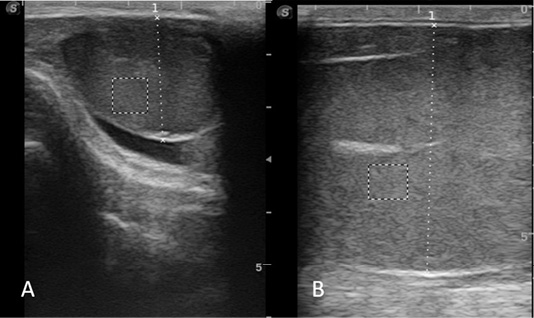

Figure 1

Ultrasound image of testis in peripubertal ram (A) and postpubertal ram (B).